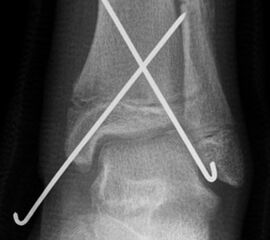

Behandlungsziel ist die exakte Rekonstruktion der Gelenkfläche sowie die Minimierung des Risikos einer späteren Wachstumsstörung. Dislozierte Frakturen werden offen reponiert, die Osteosynthese erfolgt mit einer Kleinfragmentschraube. Finden sich viele kleine Fragmente kann eine K-Draht Osteosynthese durchgeführt werden. Wird der Innenknöchel operiert, kann bei gleichzeitiger hochgradiger lateraler Instabilität eine Rekonstruktion des lateralen Bandapparats durchgeführt werden. Fibula Frakturen stellen sich meist spontan ein, sodass hier keine zusätzliche Osteosynthese notwendig ist.

Nach der Osteosynthese wird die Fraktur für ca. vier Wochen in einem Unterschenkelgips ruhiggestellt. Bei Schmerzfreiheit der Frakturzone erfolgt anschließend eine schmerzadaptierte Belastungssteigerung über weitere zwei Wochen. Sobald unter Alltagsbedingungen Beschwerdefreiheit besteht kann die sportliche Belastung langsam gesteigert werden. Kirschnerdrähte werden 6-8 Wochen postoperativ, Schrauben nach zwölf Wochen entfernt. Es empfiehlt sich klinische und radiologische Kontrollen im Abstand von 6 Monaten bis zum Wachstumsabschluss durchzuführen, um ein mögliches Fehlwachstum frühzeitig zu erkennen.